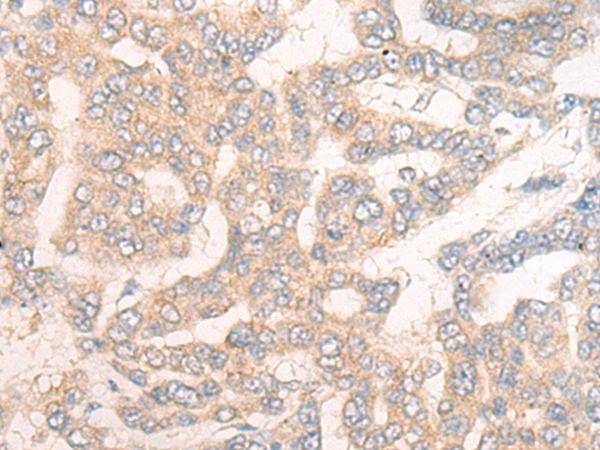

IHC positive control: |

Human liver cancer |